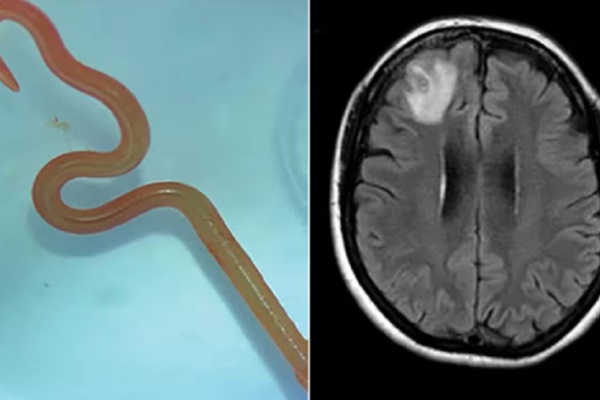

Cận cảnh con giun và vùng não thể hiện tình trạng bất thường ở bệnh nhân.

Đến tháng 1/2022, người phụ nữ bắt đầu mắc chứng hay quên và dấu hiệu trầm cảm ngày càng trầm trọng. Những triệu chứng này khiến các bác sỹ phải kiểm tra não của bà. Họ nhận thấy bà có một tổn thương trong não và chỉ định phẫu thuật. Trong ca mổ, các bác sỹ rất sốc khi nhìn thấy một con giun ký sinh trong não và họ càng choáng váng hơn khi nó ngọ nguậy.

Sau khi phân tích, họ xác định đây là một con giun đũa có tên khoa học Ophidascaris robertsi. Đội ngũ y bác sĩ của Bệnh viện Canberra cho rằng đây là trường hợp đầu tiên trên thế giới phát hiện giun đũa trong não người.

Con giun lấy ra từ não bệnh nhân.